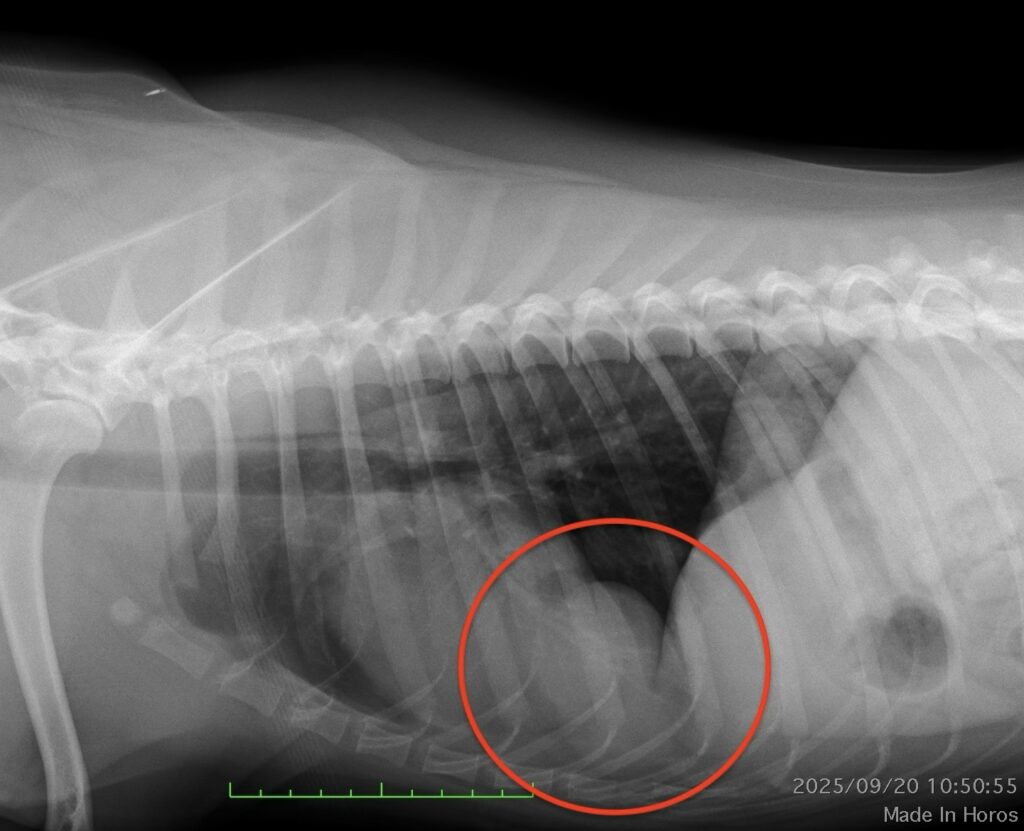

心臓尾側にmass様の陰影を認める。

エコー検査、CT検査にて胸腔内(心臓尾側)に肝臓実質(方形葉)が脱出。